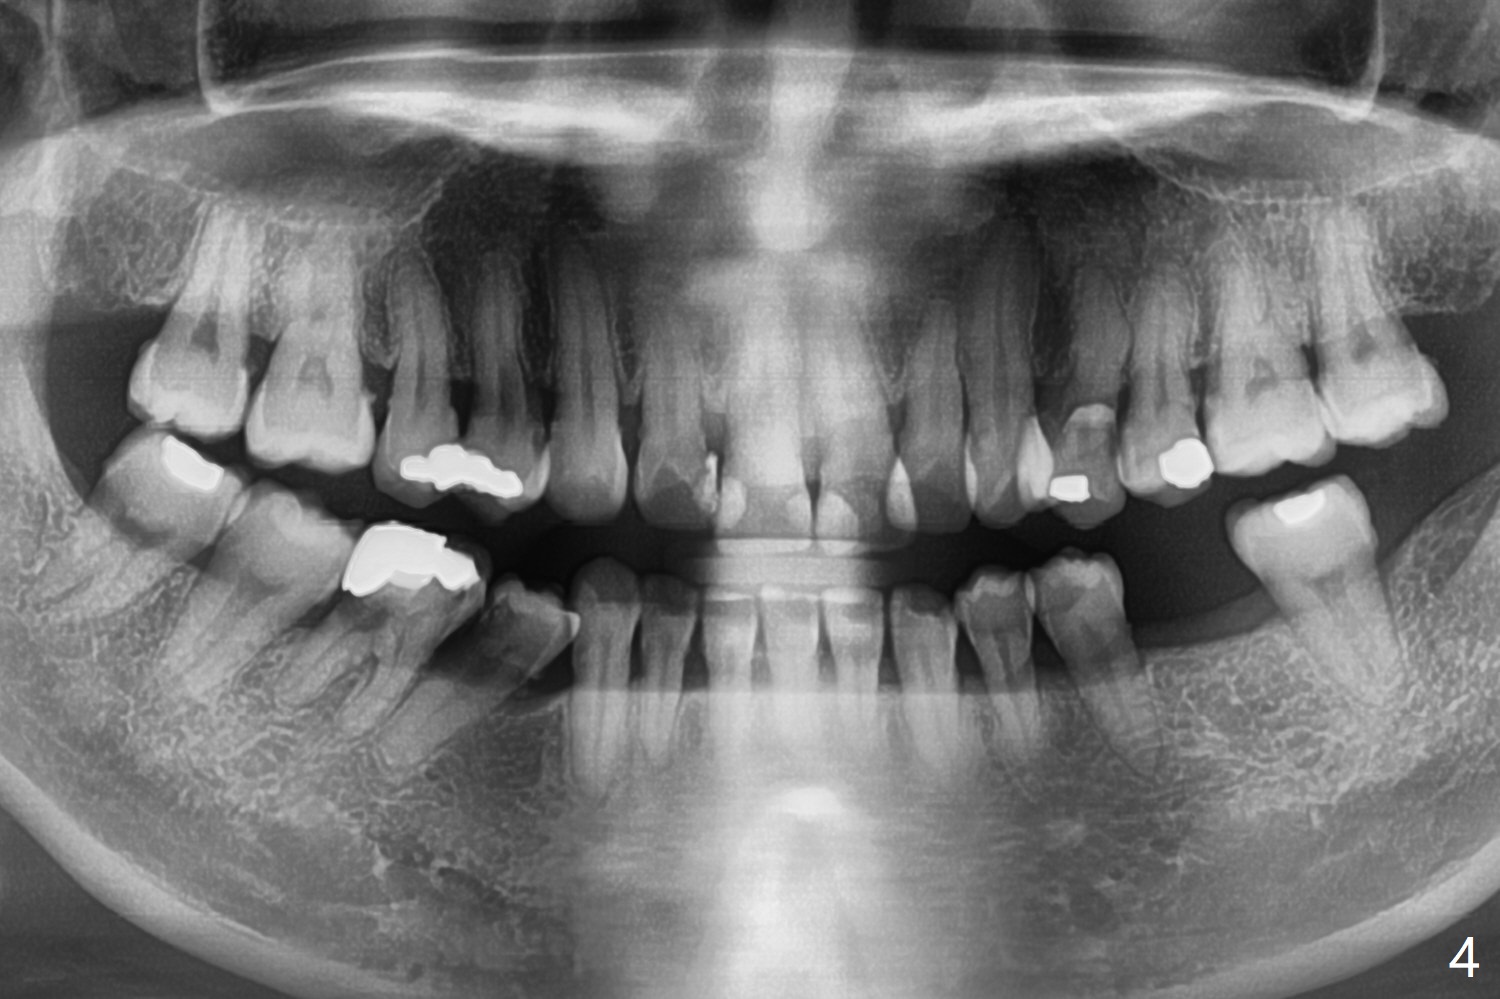

A 39-year-old woman has severe toothache associated with #30 subgingival caries (Fig.1 * distolingual). To reduce buccal plate perforation, a 4.5x11.5 mm implant will be placed (Fig.2 (bone height 15 mm). Take PA after parallel pin to make sure that blood supply to the tooth #29 is not compromised. For easy impression later, a temporary abutment will be used for immediate provisional so that a large soft tissue hemisphere is created. A cementation abutment is estimated to be 6.5x4(3) mm. Schedule SRP after implant placement (Fig.1). In fact the patient declines implant placement and accepts socket preservation (Fig.3 (*: Vanilla Graft)) because of history of hemorrhage associated with #19 extraction (Fig.4).